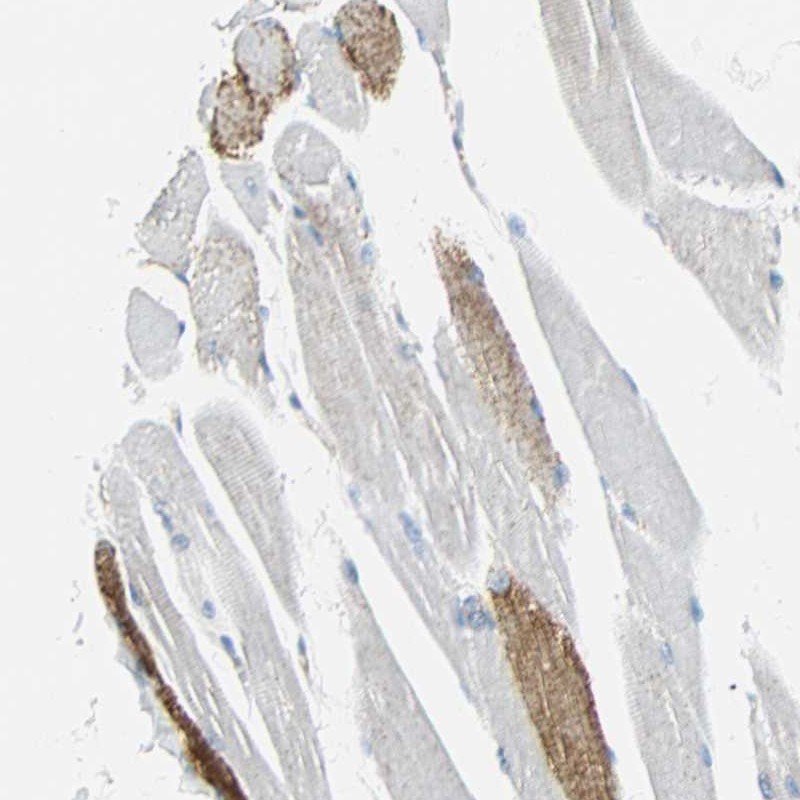

Immunohistochemical staining of human skeletal muscle shows moderate cytoplasmic positivity in myocytes.